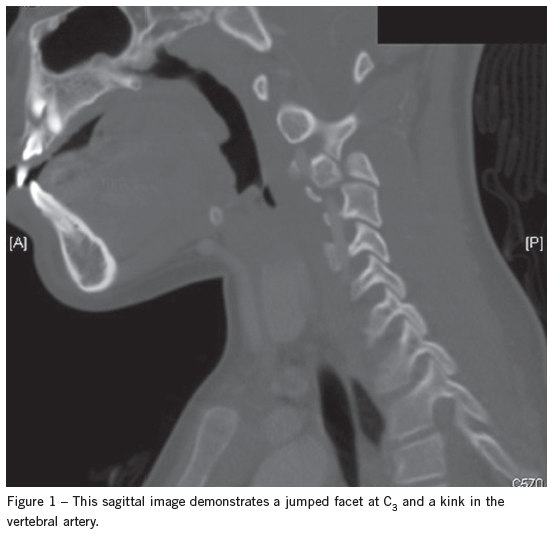

The next day the patient’s CT scan was evaluated by the attending radiologist, who found a right C3-4 facet dislocation. The child was called back to the ED for reevaluation. A neck CT scan with contrast demonstrated a jumped facet at C3, and a kink in the vertebral artery (Figure 1) and normal alignment of the left side (Figure 2).